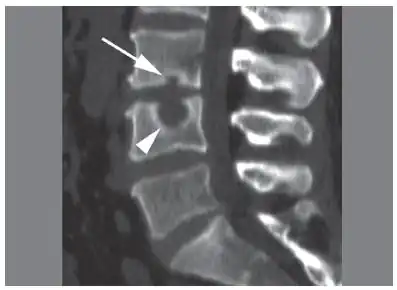

CT scan in the sagittal plane of two Schmorl's nodes. The small Schmorl's node at the inferior endplate of the L3 vertebral body (arrow) has typical features, being broad-based at the endplate, with well-defined contours and thin marginal sclerosis. A large and less typical Schmorl's node (arrowhead) is observed at the superior endplate of L4.[3]

Schmorl's nodes can be detected with X-rays, although they can be imaged better by CT or MRI. They are considered to be vertical disc herniations through the cartilaginous vertebral body endplates. Schmorl's nodes can sometimes be seen radiographically, however they are more often seen on MRI, even when not visible on plain X-rays. They may or may not be symptomatic, and their etiological significance for back pain is controversial. In a study in Spine by Hamanishi, et al., Schmorl's nodes were observed on MRI in 19% of 400 patients with back pain, and in only 9% of an asymptomatic control group. The authors concluded that Schmorl's nodes are areas of "vertical disc herniation" through areas of weakness in the endplate.[4]